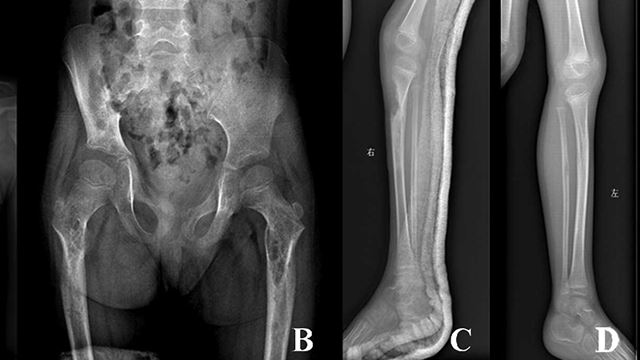

Doktor Terkejut Dan Tidak Tahu Punca Bagaimana Tulang Pesakitnya Hilang Secara Tiba-tiba

Doktor Kehairanan Tatkala Tulang Badan Hilang